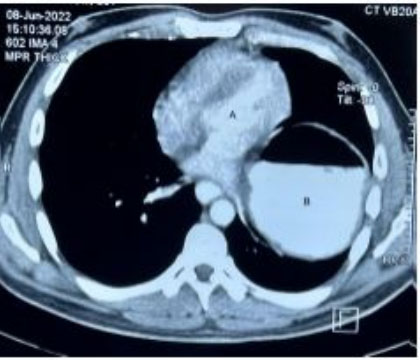

Similar to the first case mentioned above, difficulty was faced while attempting upper GI endoscopy and the scope could not be negotiated. Further evaluation with CT scan revealed displacement of the stomach into the left hemi-thorax (Figure 6 and Figure 7).

Figure 6: Contrast CT scan, coronal view showing displacement of the stomach (A) in to the left mediastinum.

Figure 7: Contrast CT scan, transverse section showing the stomach (B) located within the chest cavity just beside the heart (A).